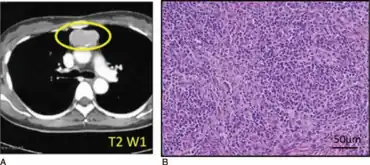

Individual with Good syndrome a) Computed tomography findings demonstrating mediastinal abnormality b) thymus gland specimen was stained with hematoxylin/eosin

Thymoma with immunodeficiency (also known as "Good syndrome") is a rare disorder that occurs in adults in whom hypogammaglobulinemia, deficient cell-mediated immunity, and thymoma (usually benign) may develop almost simultaneously.[1]:82[2] Most reported cases are in Europe, though it occurs globally.[3]